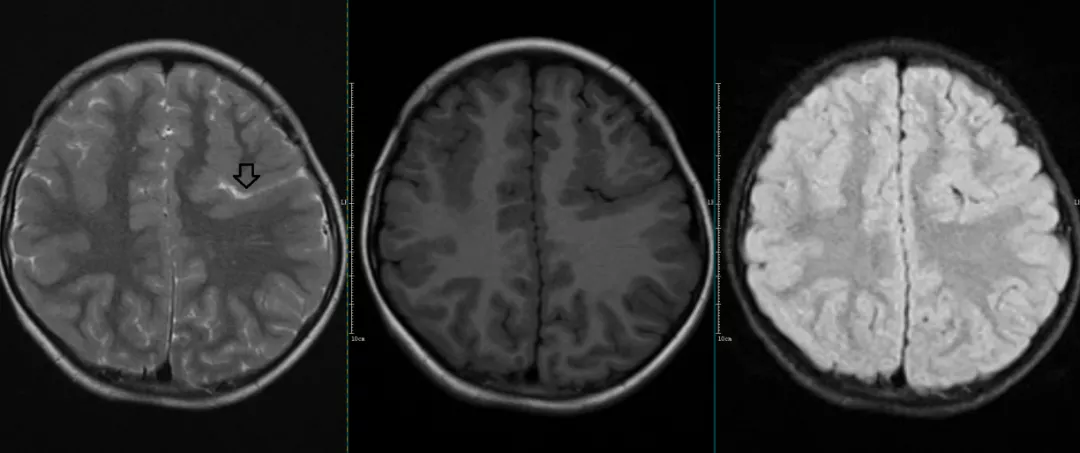

一侧脑室增大(侧脑室不对称)

通常情况下,两侧侧脑室结构对称,但正常脑室的大小与形态也存在个体差异,5~10%的正常人可以出现两侧侧脑室不对称,可能是胚胎发育异常所致的解剖变异。MRI表现为一侧脑室增大,透明隔可以跨越中线向对侧移位,无占位效应,在各个序列上脑室内和脑室周围均无异常信号。

诊断发育性侧脑室不对称时必须要除外脑室内各种炎性粘连(如感染性、异物及化学物质刺激性、外伤后)或潜在的占位引起的病理性增大以及梗阻性病变。

CASE1

右侧脑室较对侧大